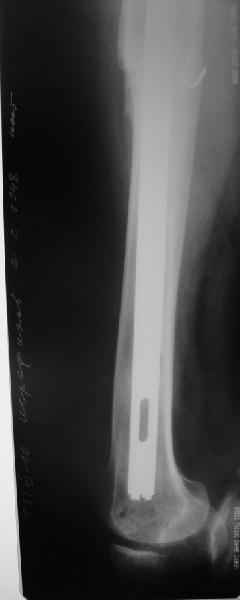

Пациенту 72 года, оперировался 11 лет назад в ГКБ15 Москва. Судя по снимку ножка споторно фирмы матис. Вряд ли сможем найти такую же для примерки.

Дополнительные снимки

Пациента удалось осмотреть недавно. Достигнутый результат сохраняется. Перелом бедра сросся. Конечность опорная и безболезненная, ходит без трости. Ножка, похоже, реинтегрировалась, как и надеялись. Снимки и фото в приложении. Комментарии приветствуются.

Надо ли что-то делать дальше, как полагаете? Убрать винты? Убрать "удлинитель ножки"? Или оставить все, как есть? Спасибо заранее.